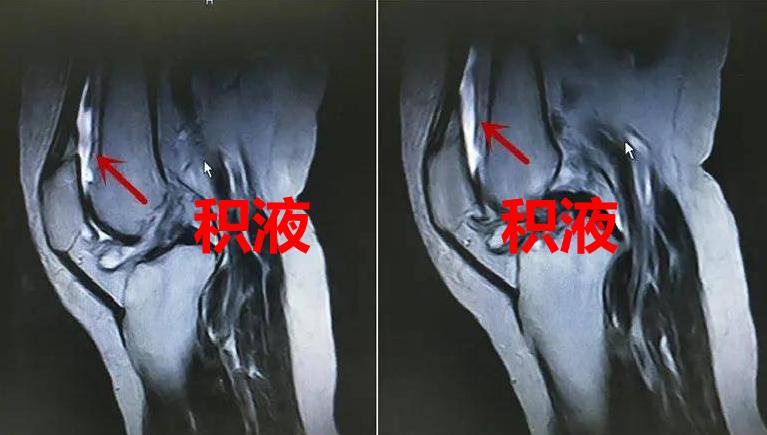

前几天在小区广场锻炼时,右腿突然感觉不舒服,一看右膝盖又红又肿。去医院检查才发现是退行性膝关节炎,膝关节积液严重。

如果关节液的排出功能下降,就会出现积液的情况。不仅关节腔被撑起来,导致整个关节韧带的受力被影响,同时代谢废物还在关节软骨和半月板的周围堆积着,影响细胞的正常活动。

从外观看,就是膝关节肿起来了。症状轻的患者觉得不太舒服,症状重的会觉得膝盖疼痛,更严重的甚至走不了路。长期发展下去,总有一天会导致膝关节变形。